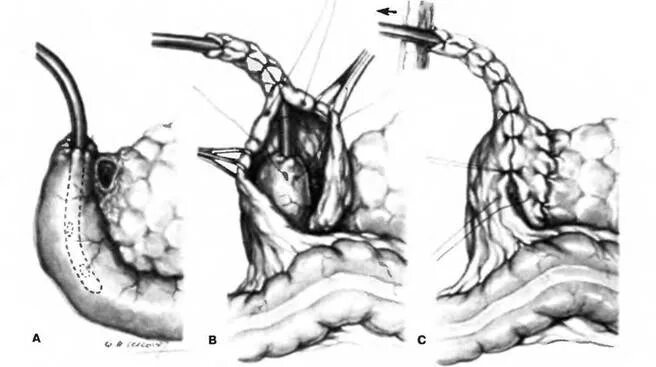

2 месяца после операции на кишечнике